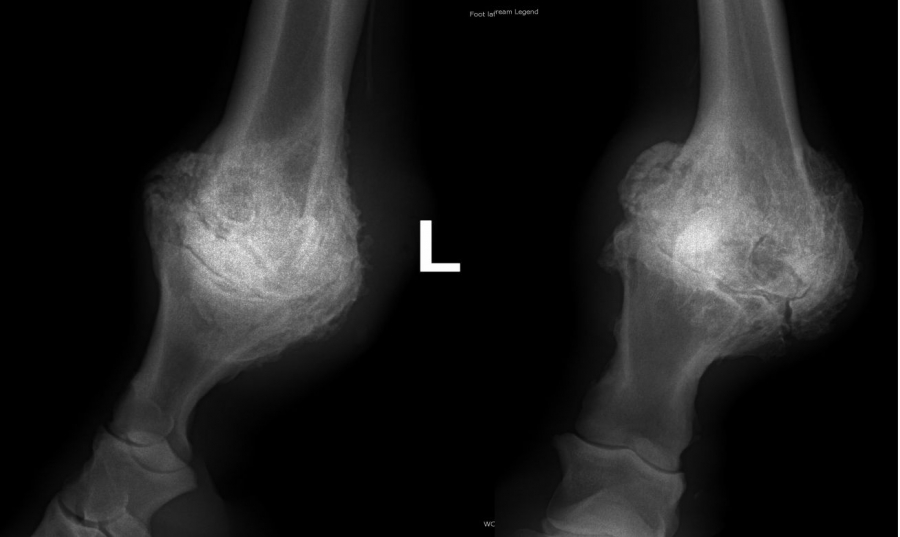

Těžká artróza ve spěnkovém kloubu

rentgenologické vyšetření